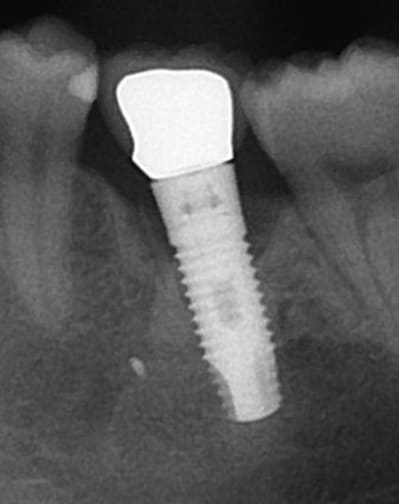

(PS la 2e pièce jointe c'est la pano)

Et une idée pour celui là?

Un zimmer screw-vent 4.7?

Oui le deuxième est un tsv